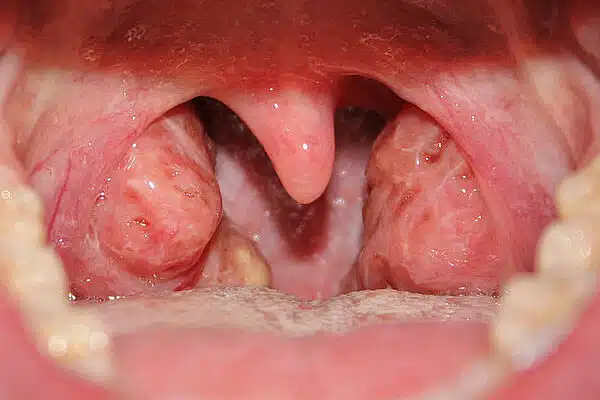

اللوزتان هما عبارة عن وسادتين يقعان في الجزء الخلفي من الحلق ، وهما مغروستان في جانب الحنك (سقف الفم). فعندما تأكل أو تشرب ، تقوم عضلات الحنجرة بدفع اللوزتين معاً ، لذلك قد تتراكم جزيئات الطعام الصغيرة في خبايا اللوزتين. وقد تؤدي هذه الجسيمات إلى إصابة اللوزتين. الناميات ( الغدانيات ) هي كتل من الانسجة تقع في الجزء الاعلى خلف الانف (البلعوم الأنفي ).

- بقع بيضاء قيحية على اللوزتين

- تضخم اللوزتين أو مظهر غير طبيعي